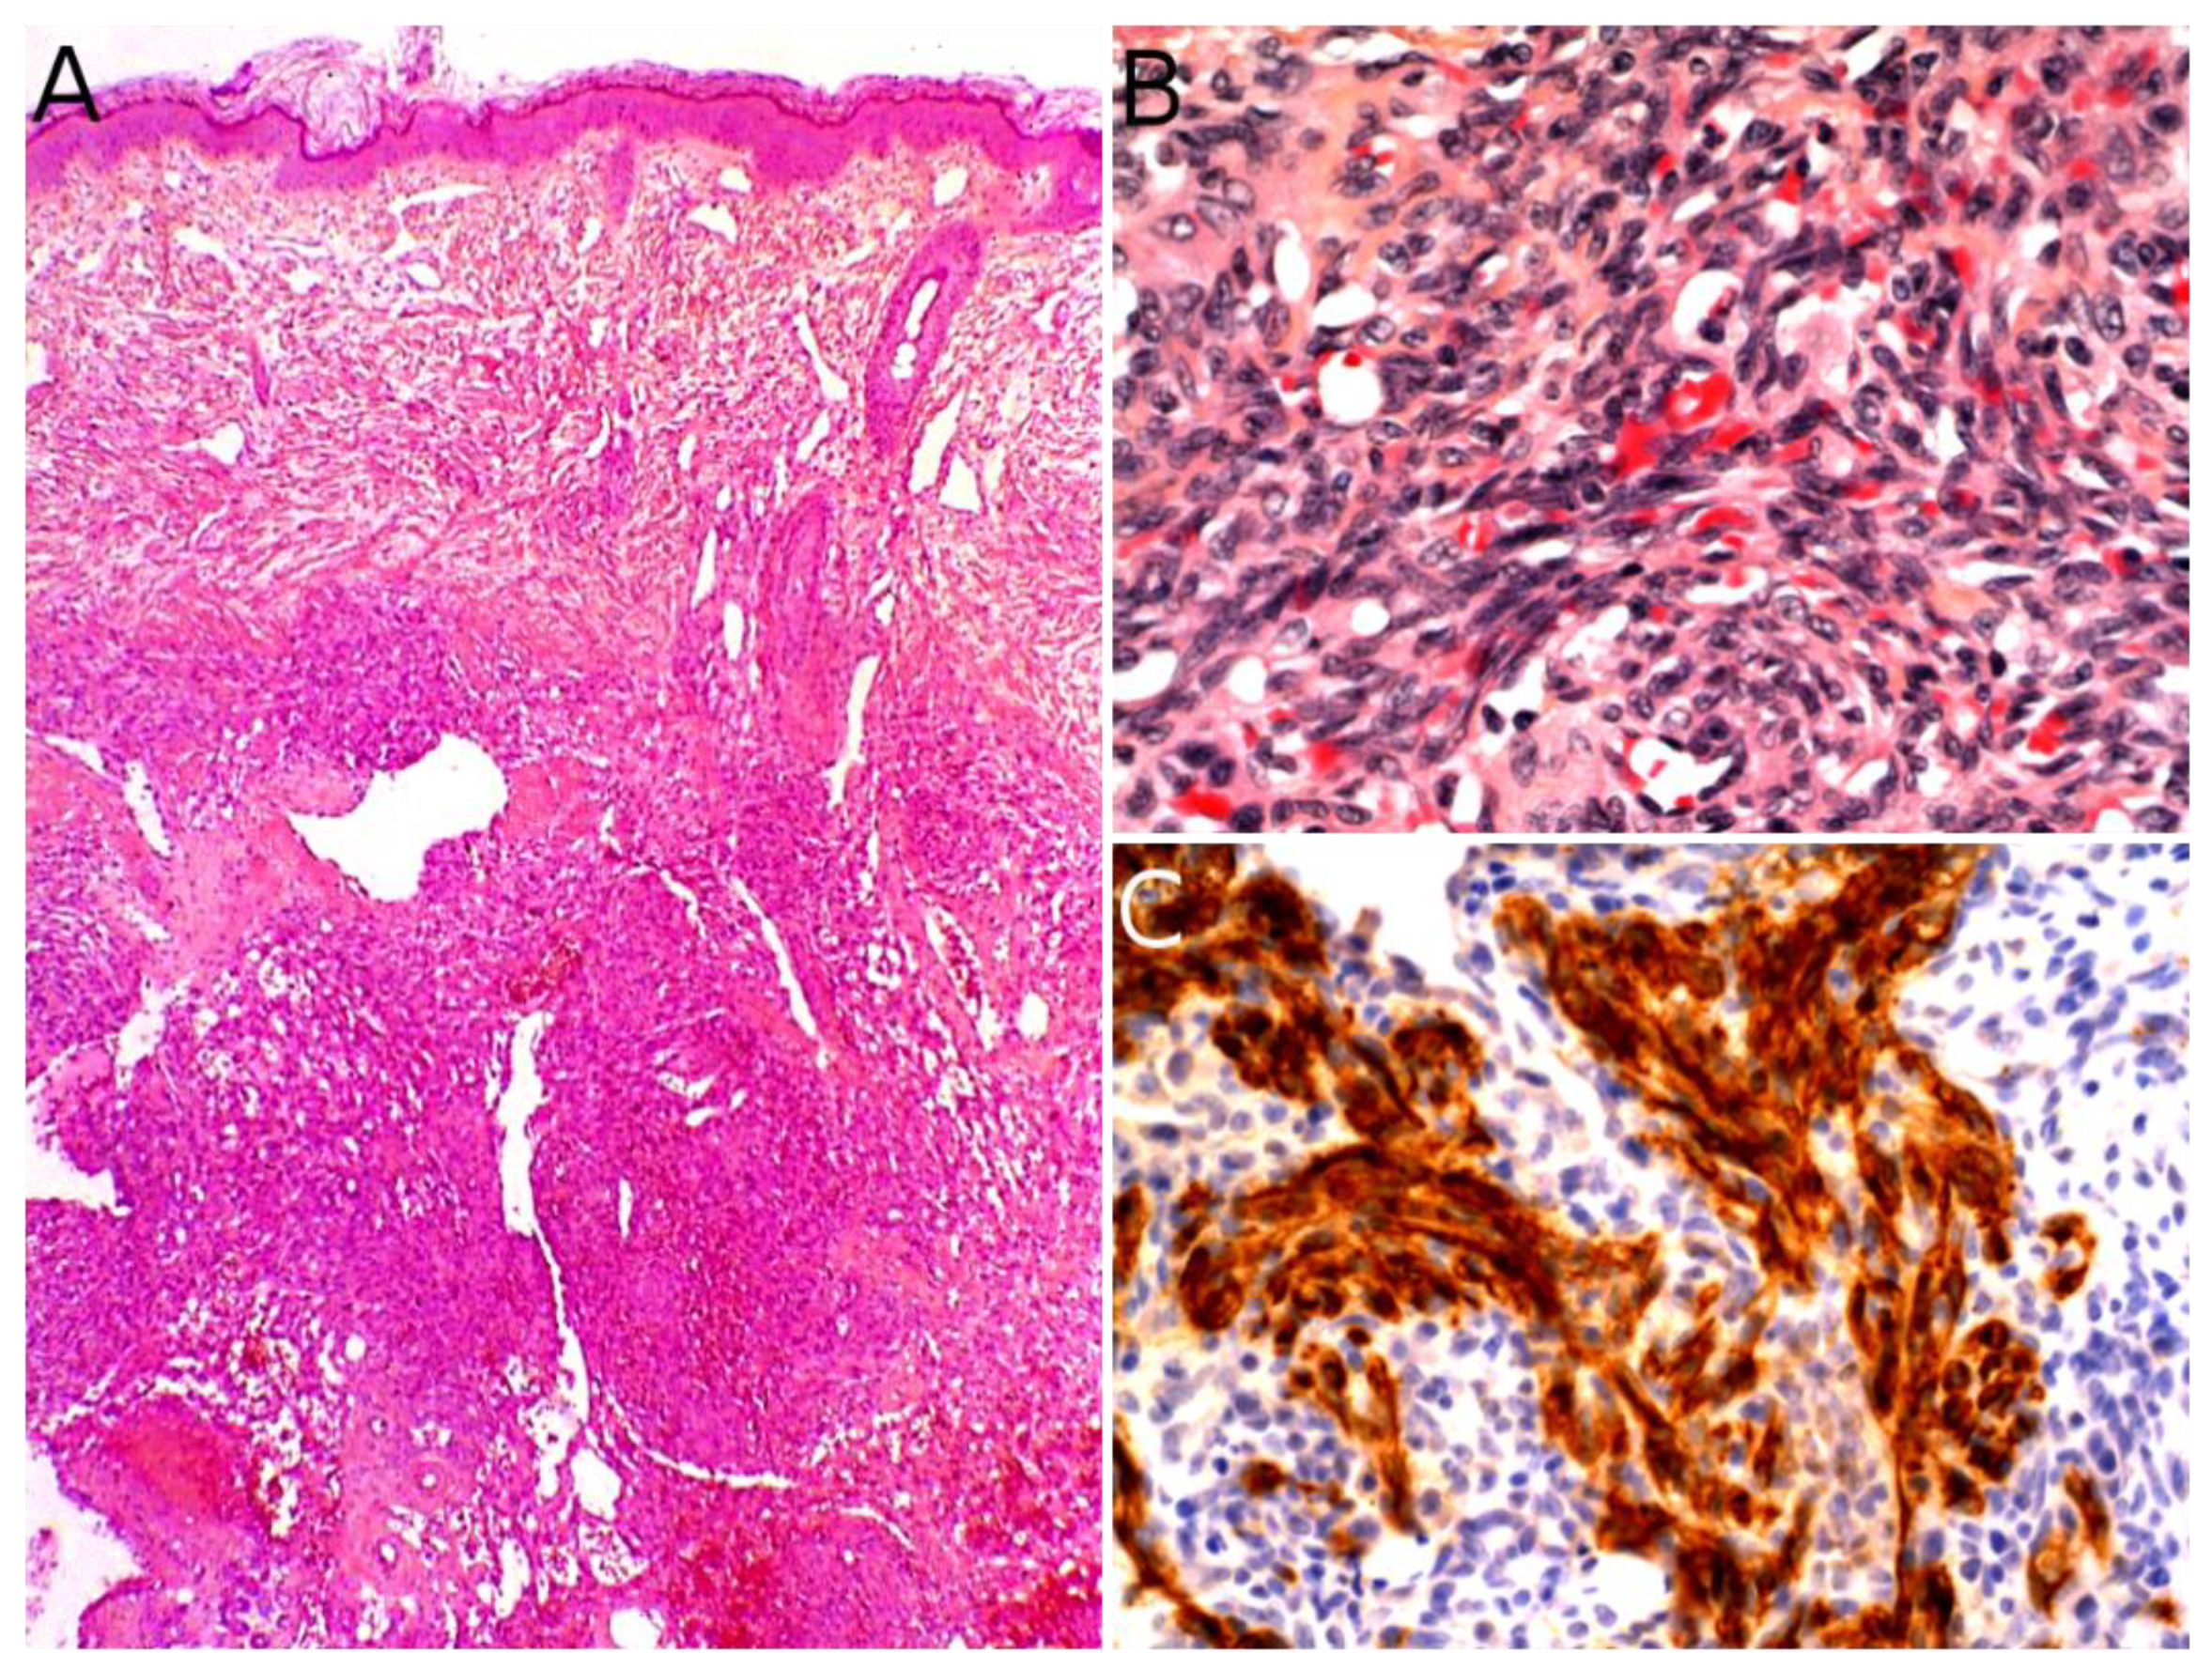

The gold standard for diagnosis is the biopsy. KHE is a deep dermal and subcutaneous, infiltrating proliferation of spindle endothelial cells arranged in nodules (Figure 7A). The tumor can adopt a “cannonball” pattern, especially in the dermis, similar to a tufted angioma, but the nodules are larger, less defined, and coalescent. The tumor is also more infiltrative. Mitoses are rare and not abnormal (Figure 7B) [78,80,85]. Most of the spindle cells are positive for lymphatic markers podoplanin, LYVE1, and PROX1 (Figure 7C) [80,86].

Figure 7.

Kaposiform hemangioendothelioma: (A) Deep dermal and subcutaneous, infiltrating proliferation of spindle cells arranged in nodules (×25); (B) spindle endothelial cells with no mitoses (×200); (C) positivity for the lymphatic marker podoplanin in the spindle cells (×200).